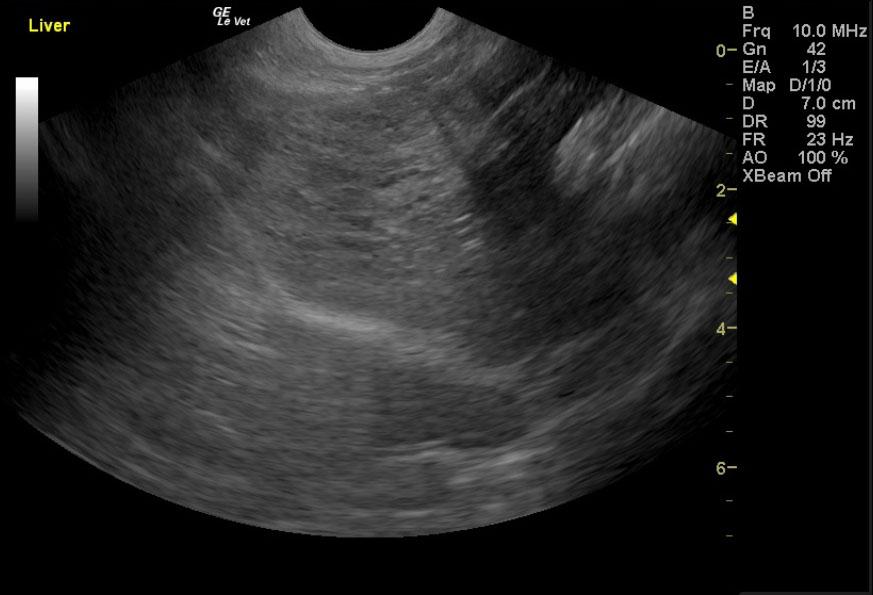

Image Interpretation

Deep right liver mass impinging upon the diaphragm and vena cava dorsally; the mass is likely not resectable. This is probably a cystadenoma, but adenocarcinoma is possible. A right perirenal cyst with a concurrent renal cortical cyst is noted in the right kidney. There is significant renal dystrophy of both kidneys, with pyelectasia or potential concurrent urinary tract infection.